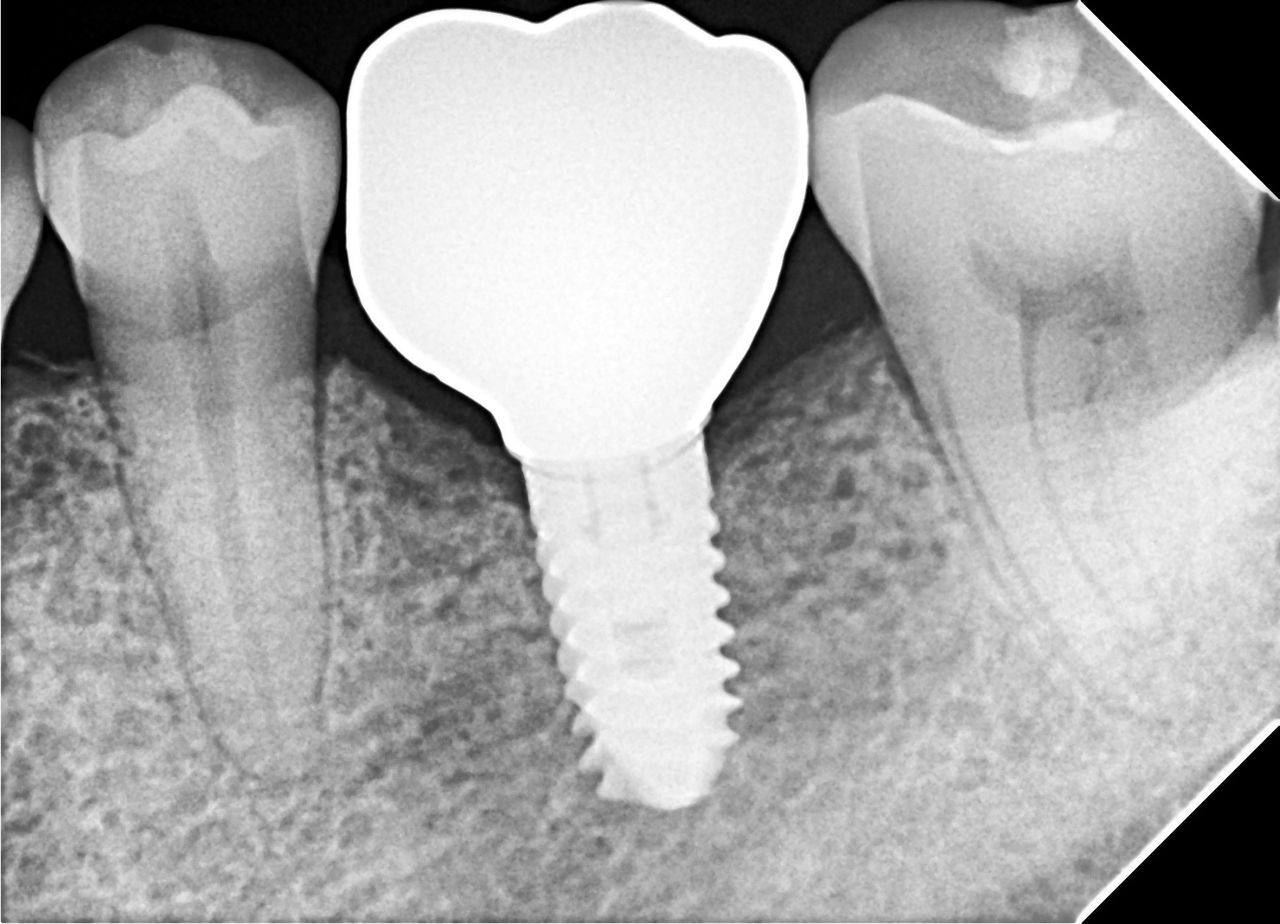

Colocación de implantes con tecnología avanzada

Hoy realizamos la colocación de dos implantes dentales, un procedimiento planificado y ejecutado con guía quirúrgica de implantes, lo que nos permite obtener una colocación más exacta, segura y predecible